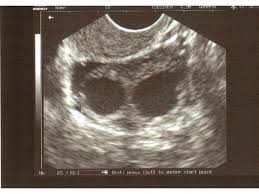

ej Dziewczyny.Mam pytanie, ostatnio byłam na wizycie u mojego lekarza który potwierdził na usg dwa pęcherzyki ( jeden większy a drugi mniejszy) powiedział że wygląda mu to na ciąże bliźniaczą ale te nie wyklucza małego krwiaka.Czy ktoś miał podobną sytuację a potem okazało się że biją dwa serduszka? wizytę mam dopiero za 10 dni a już warjuje. Zdjęcie jest bardzo podobne z tym że jeden pęcherzyk jest trochę mniejszy.